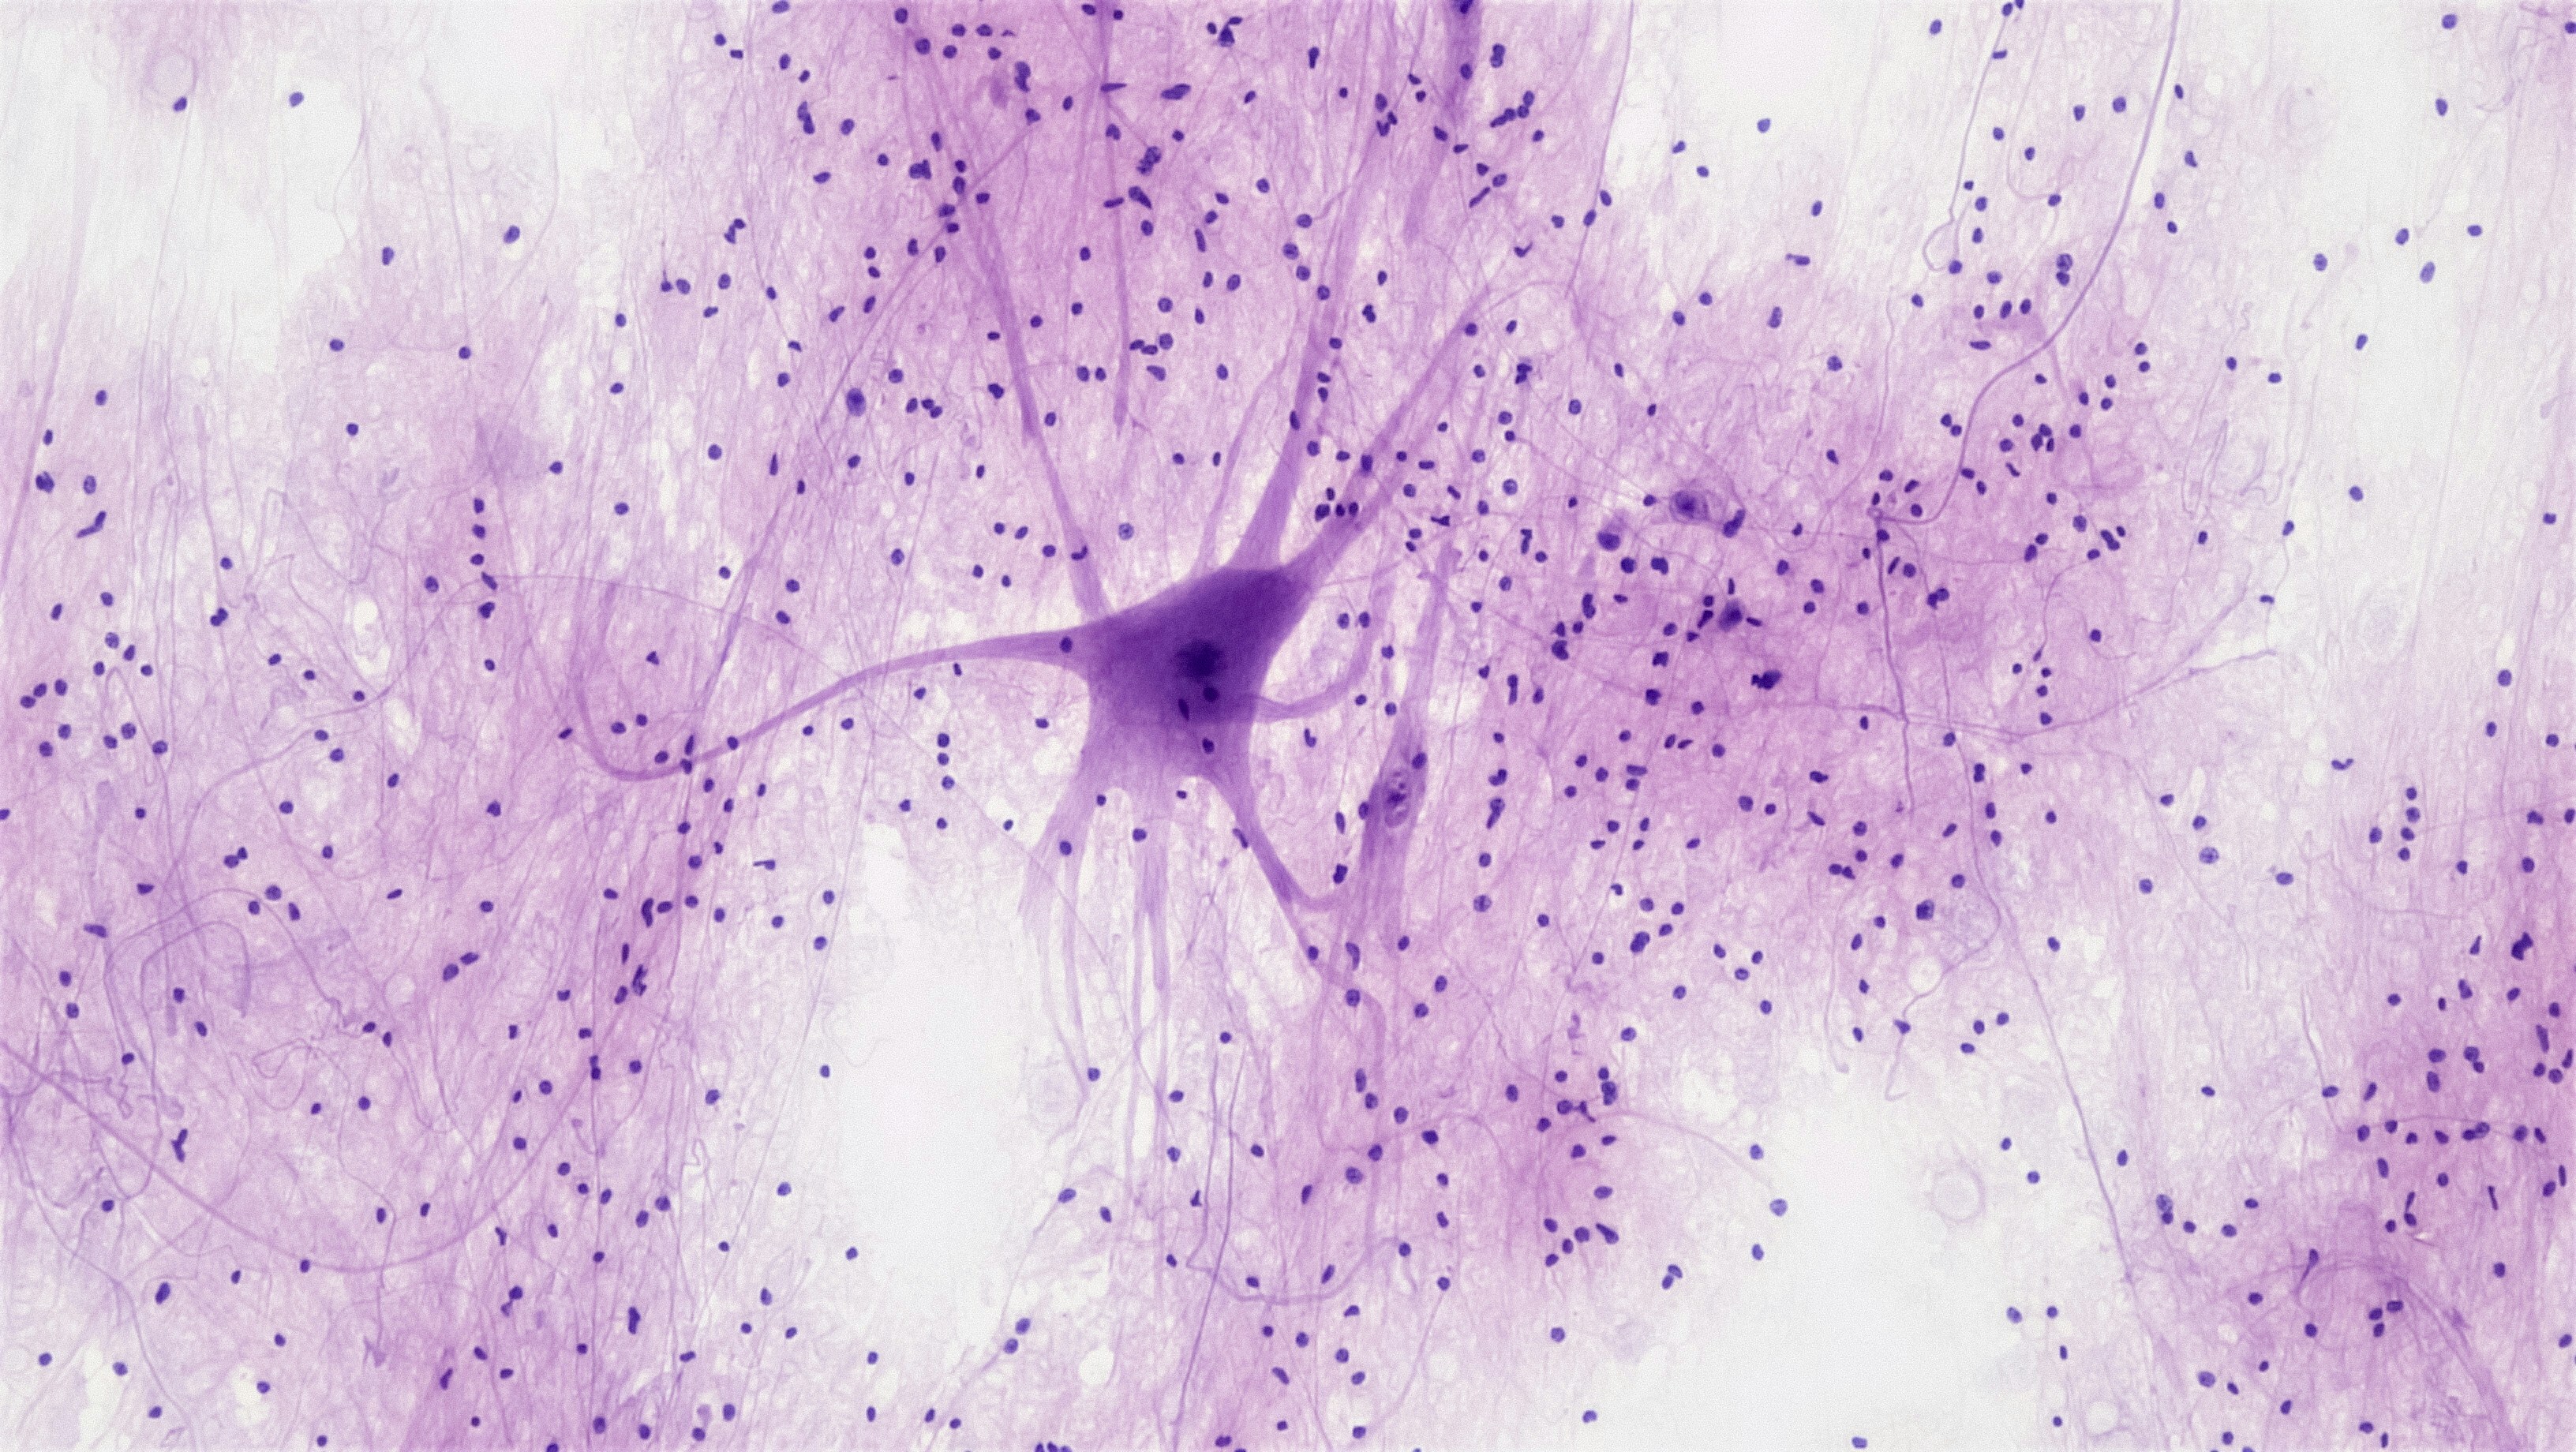

Ученые Белгородский государственный национальный исследовательский университет (НИУ «БелГУ») предложили новый метод лечения травматических и сосудистых повреждений, основываясь на использовании генотерапевтических конструкций.

Это включает применение плазмид — молекул ДНК, которые могут ускорять процесс ранозаживления. . ferra.ru